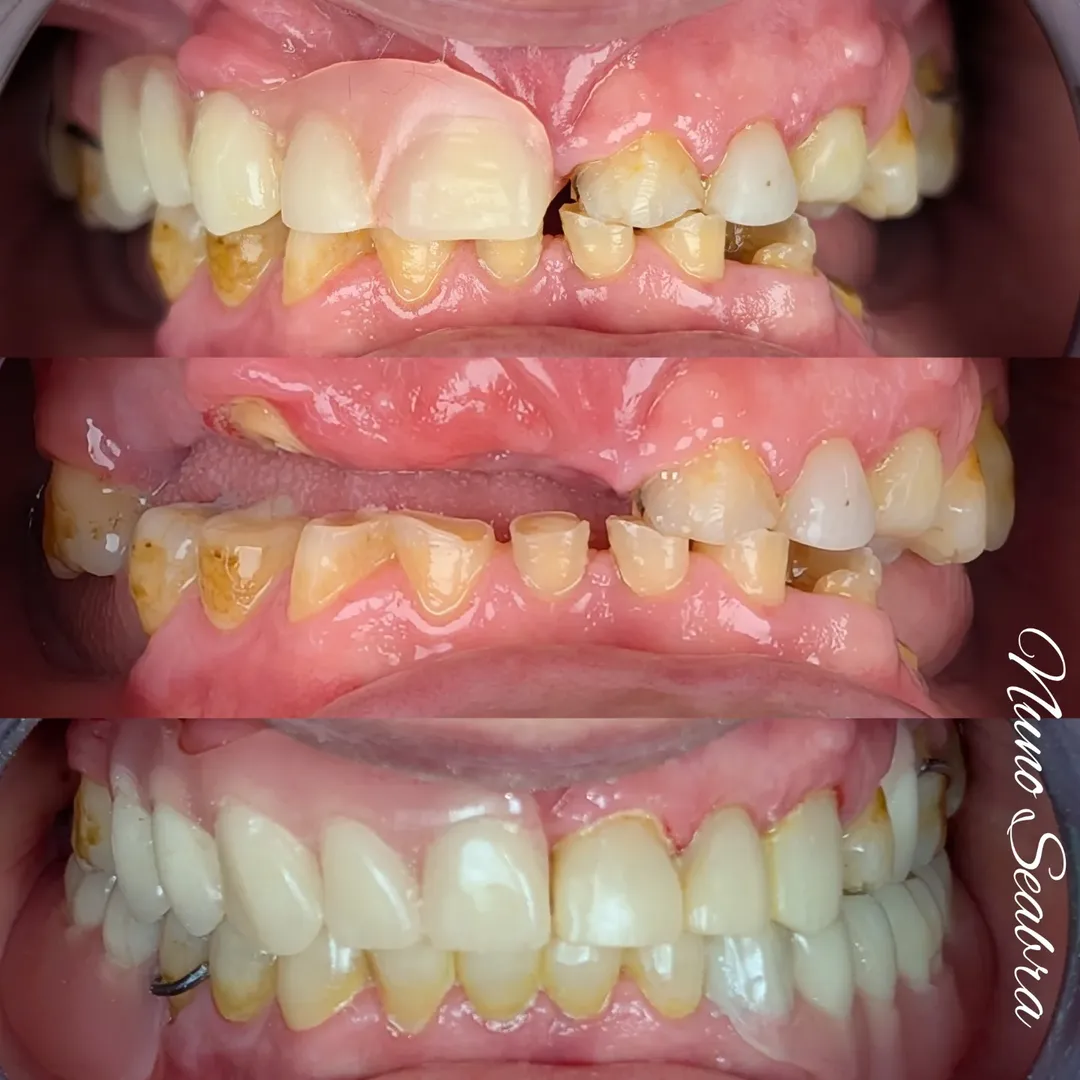

Nas imagens iniciais, vemos claramente o impacto do desgaste e da perda dentária.

Dentes fraturados, alterações no sorriso e uma grande limitação funcional e estética. A simples colocação de próteses convencionais resolveria parcialmente o problema, mas traria desconforto e necessidade de ganchos visíveis, algo que tento sempre evitar.

A decisão foi trabalhar com novas próteses removíveis acrílicas, mas ancoradas de forma mais inteligente. Aproveitámos os dentes 13 e 33 para colocar equators, transformando as próteses em sobredentaduras (overdentures).

As sobredentaduras permitiram combinar o suporte protético com um sorriso esteticamente equilibrado, respeitando a função e a harmonia facial.

No slider de imagens, conseguimos acompanhar o processo completo: